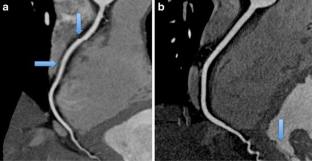

Fig. 1